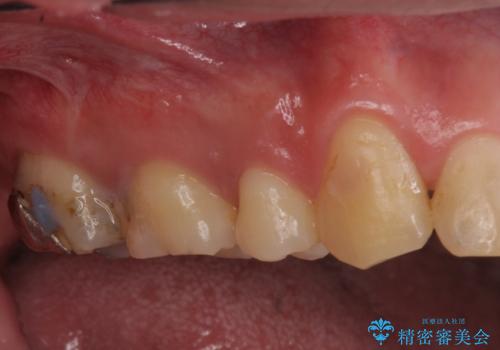

- 一番奥の銀の詰め物を白くしたいとのことで来院。

セラミックの詰め物のやりかえだと範囲が多く、割れてしまうリスクがあります。

そのため、割れるリスクが少ない詰め物ではなく、被せ物による治療(ジルコニアクラウン)を行いました。

また、隣の歯も白い樹脂の下が虫歯になっており、セラミックの詰め物(e-maxインレー)による修復をしました。